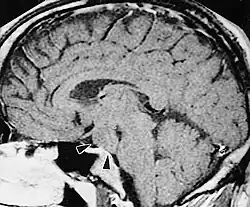

A hypothalamic hamartoma (black arrows) on MRI |

The tumor is difficult to detect by CT due to decreased sensitivity of the scan at the level of the sella turcica. MRI is the primary imaging modality for detection, with the lesion being of similar signal intensity to gray matter and non-enhancing with contrast. Lack of enhancement is an important imaging characteristic to help distinguish the tumor from similar masses that can occur in this region. These include germ cell tumors, granulomas of Langerhans cell histiocytosis and hypothalamic astrocytomas, as these lesions usually demonstrate at least partial uptake of contrast.[1]